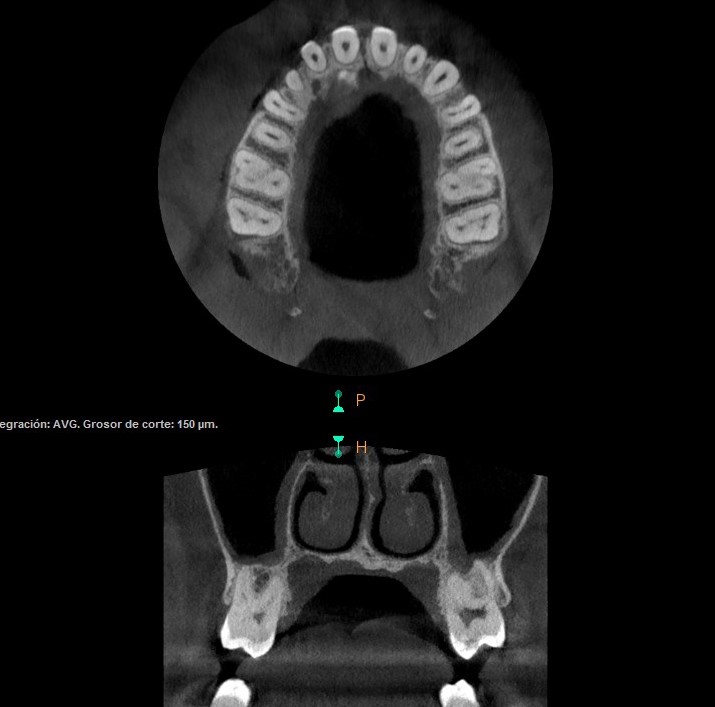

El TAC Dental 3D, también conocido como Tomografía Axial Computarizada Dental, es una técnica de diagnóstico por imágenes que permite obtener vistas tridimensionales tanto de la boca como de sus estructuras. Utilizando esta avanzada tecnología, se obtienen imágenes detalladas de los dientes, huesos y tejidos blandos, lo que facilita un diagnóstico preciso así como un tratamiento adecuado.

Se pueden ver detalles precisos de los dientes, los huesos maxilares, las articulaciones temporomandibulares, los senos paranasales y los tejidos blandos de la boca, lo que permite un diagnóstico preciso.